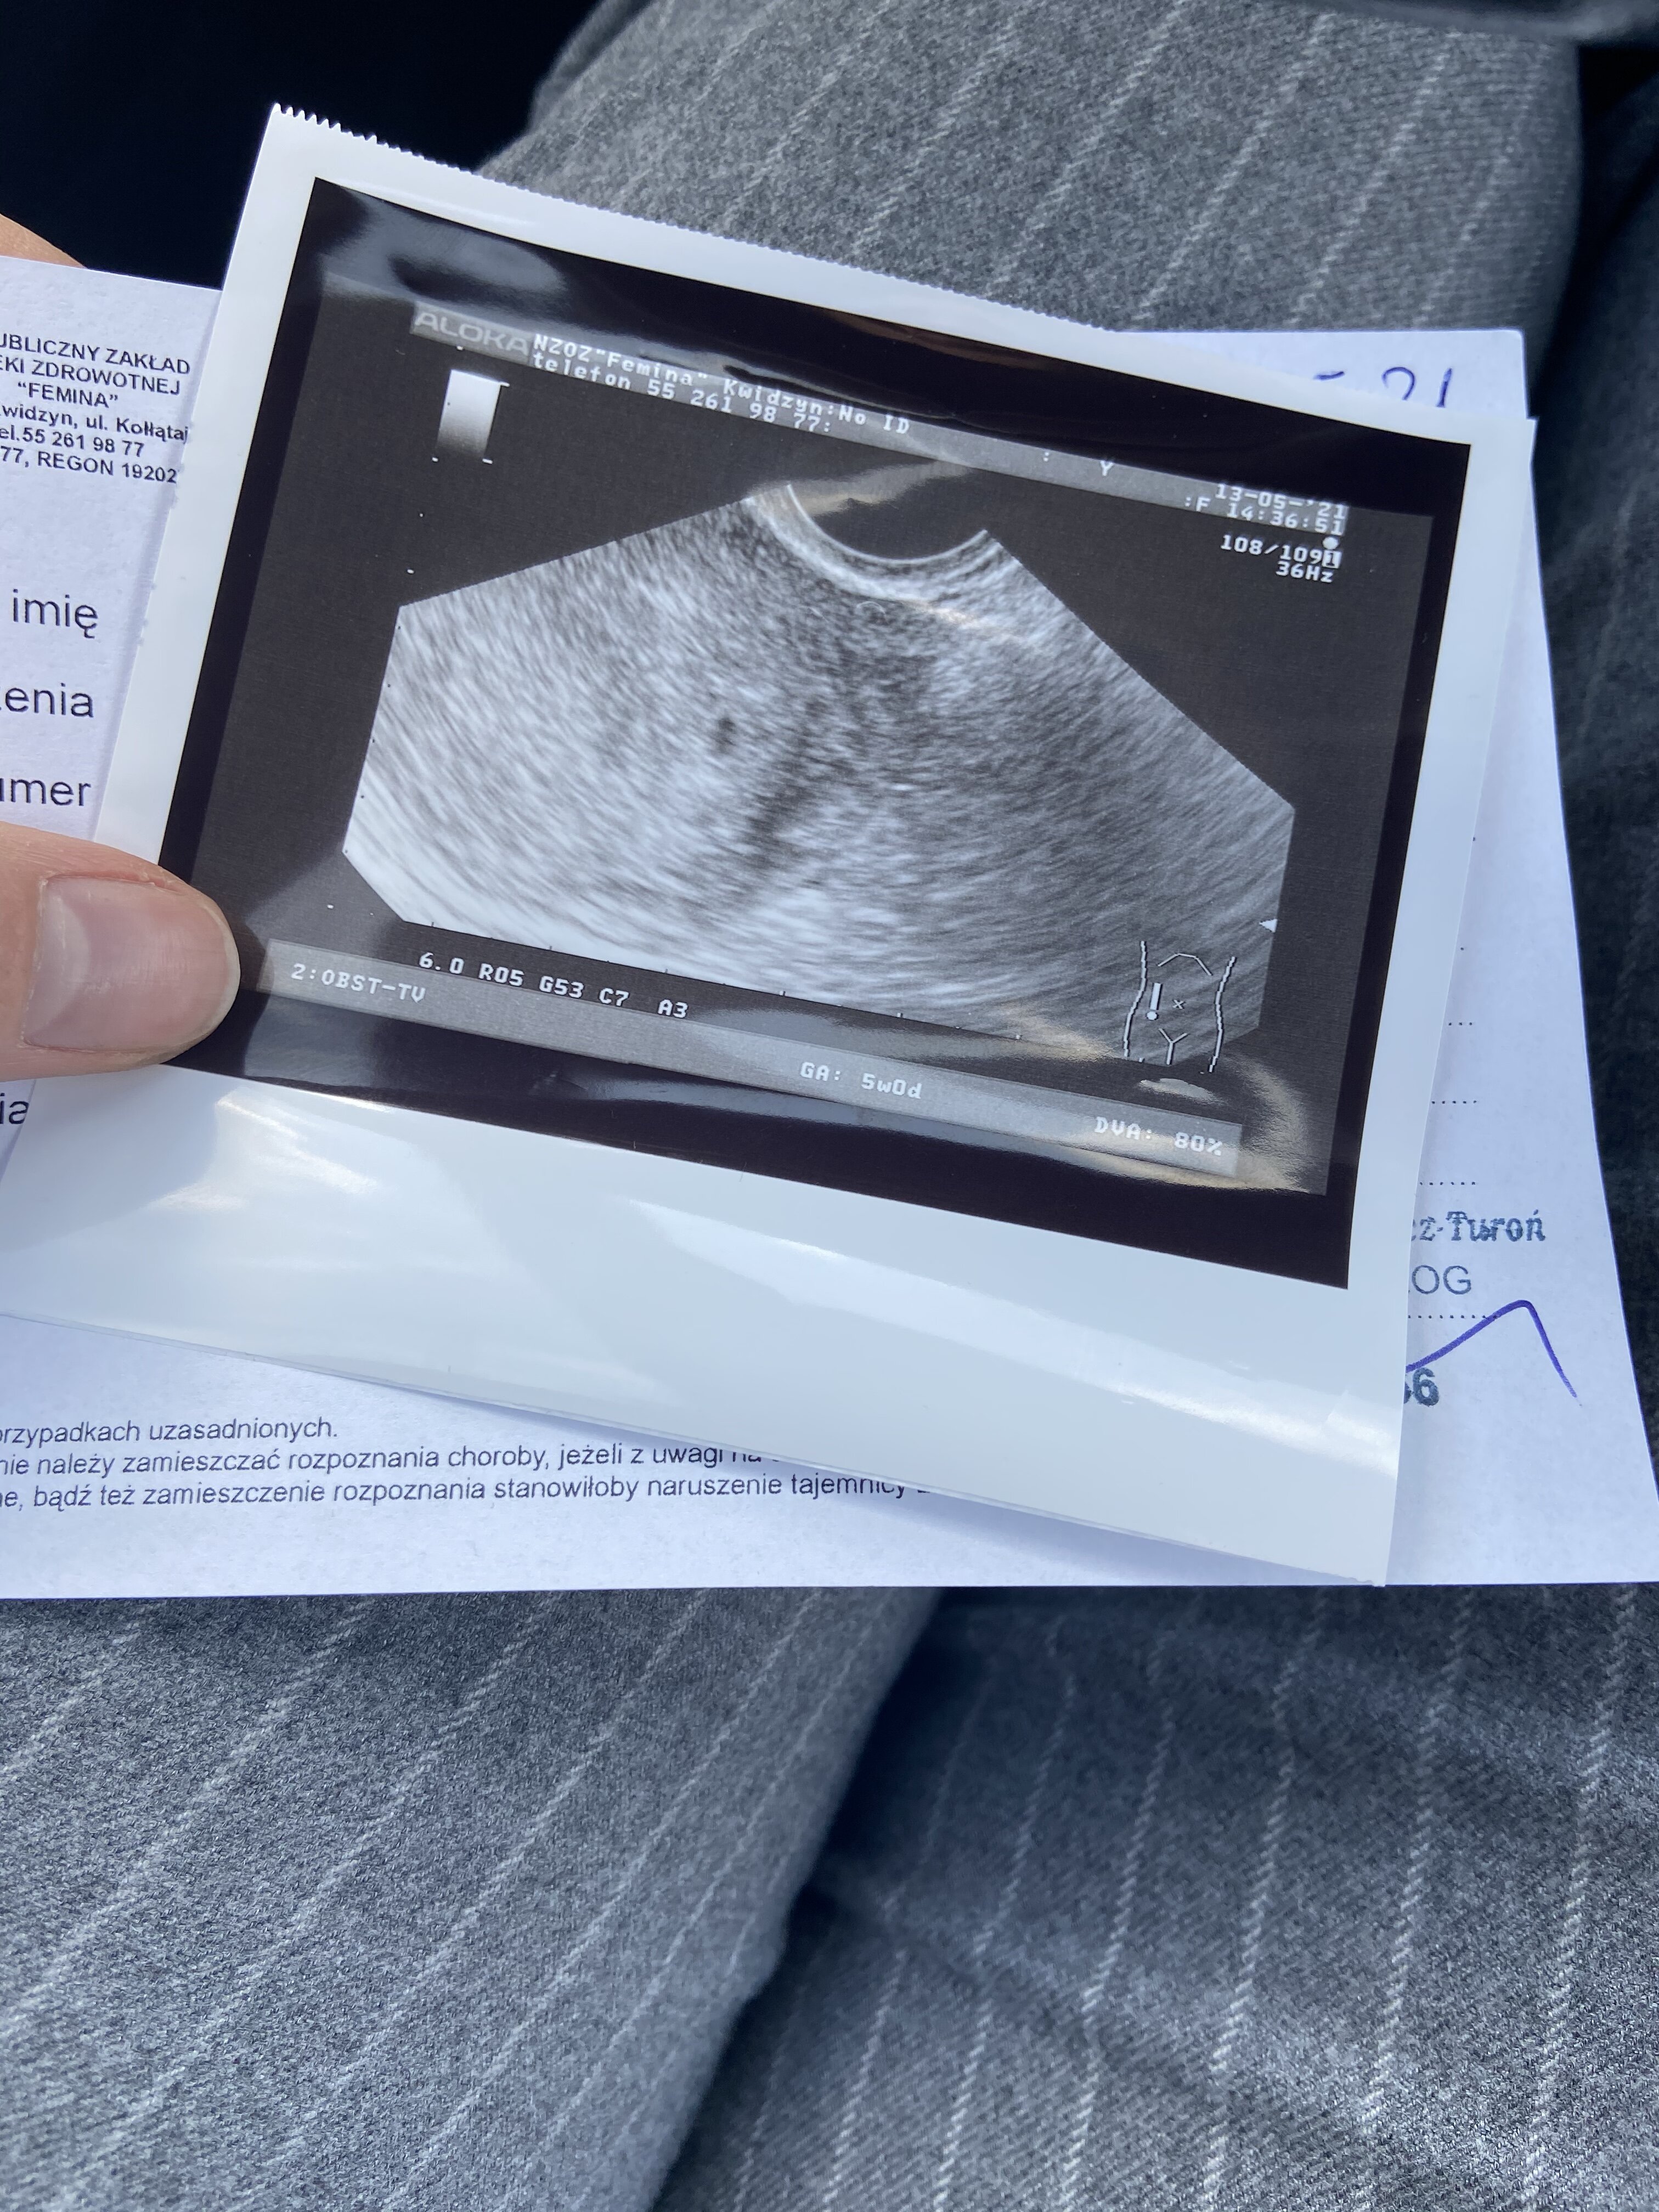

kiedy byłam w 4 tygodniu lekarz powiedział że nic nie widać, a jak byłam w 6 to robił pomiar, i znów powiedział że nic nie widać, a na USG według mnie widać. Dołączę zdjęcie.

Kazał teraz przyjść za tydzień i powiedział że jeśli będzie ok, to założy kartę ciąży

Dołączam

Załączniki

• 2d39c9b3-8d73-4c65-b5c7-becf23119ebd.jpg

2d39c9b3-8d73-4c65-b5c7-becf23119ebd.jpg

51,7 KB · Wyświetleń: 153